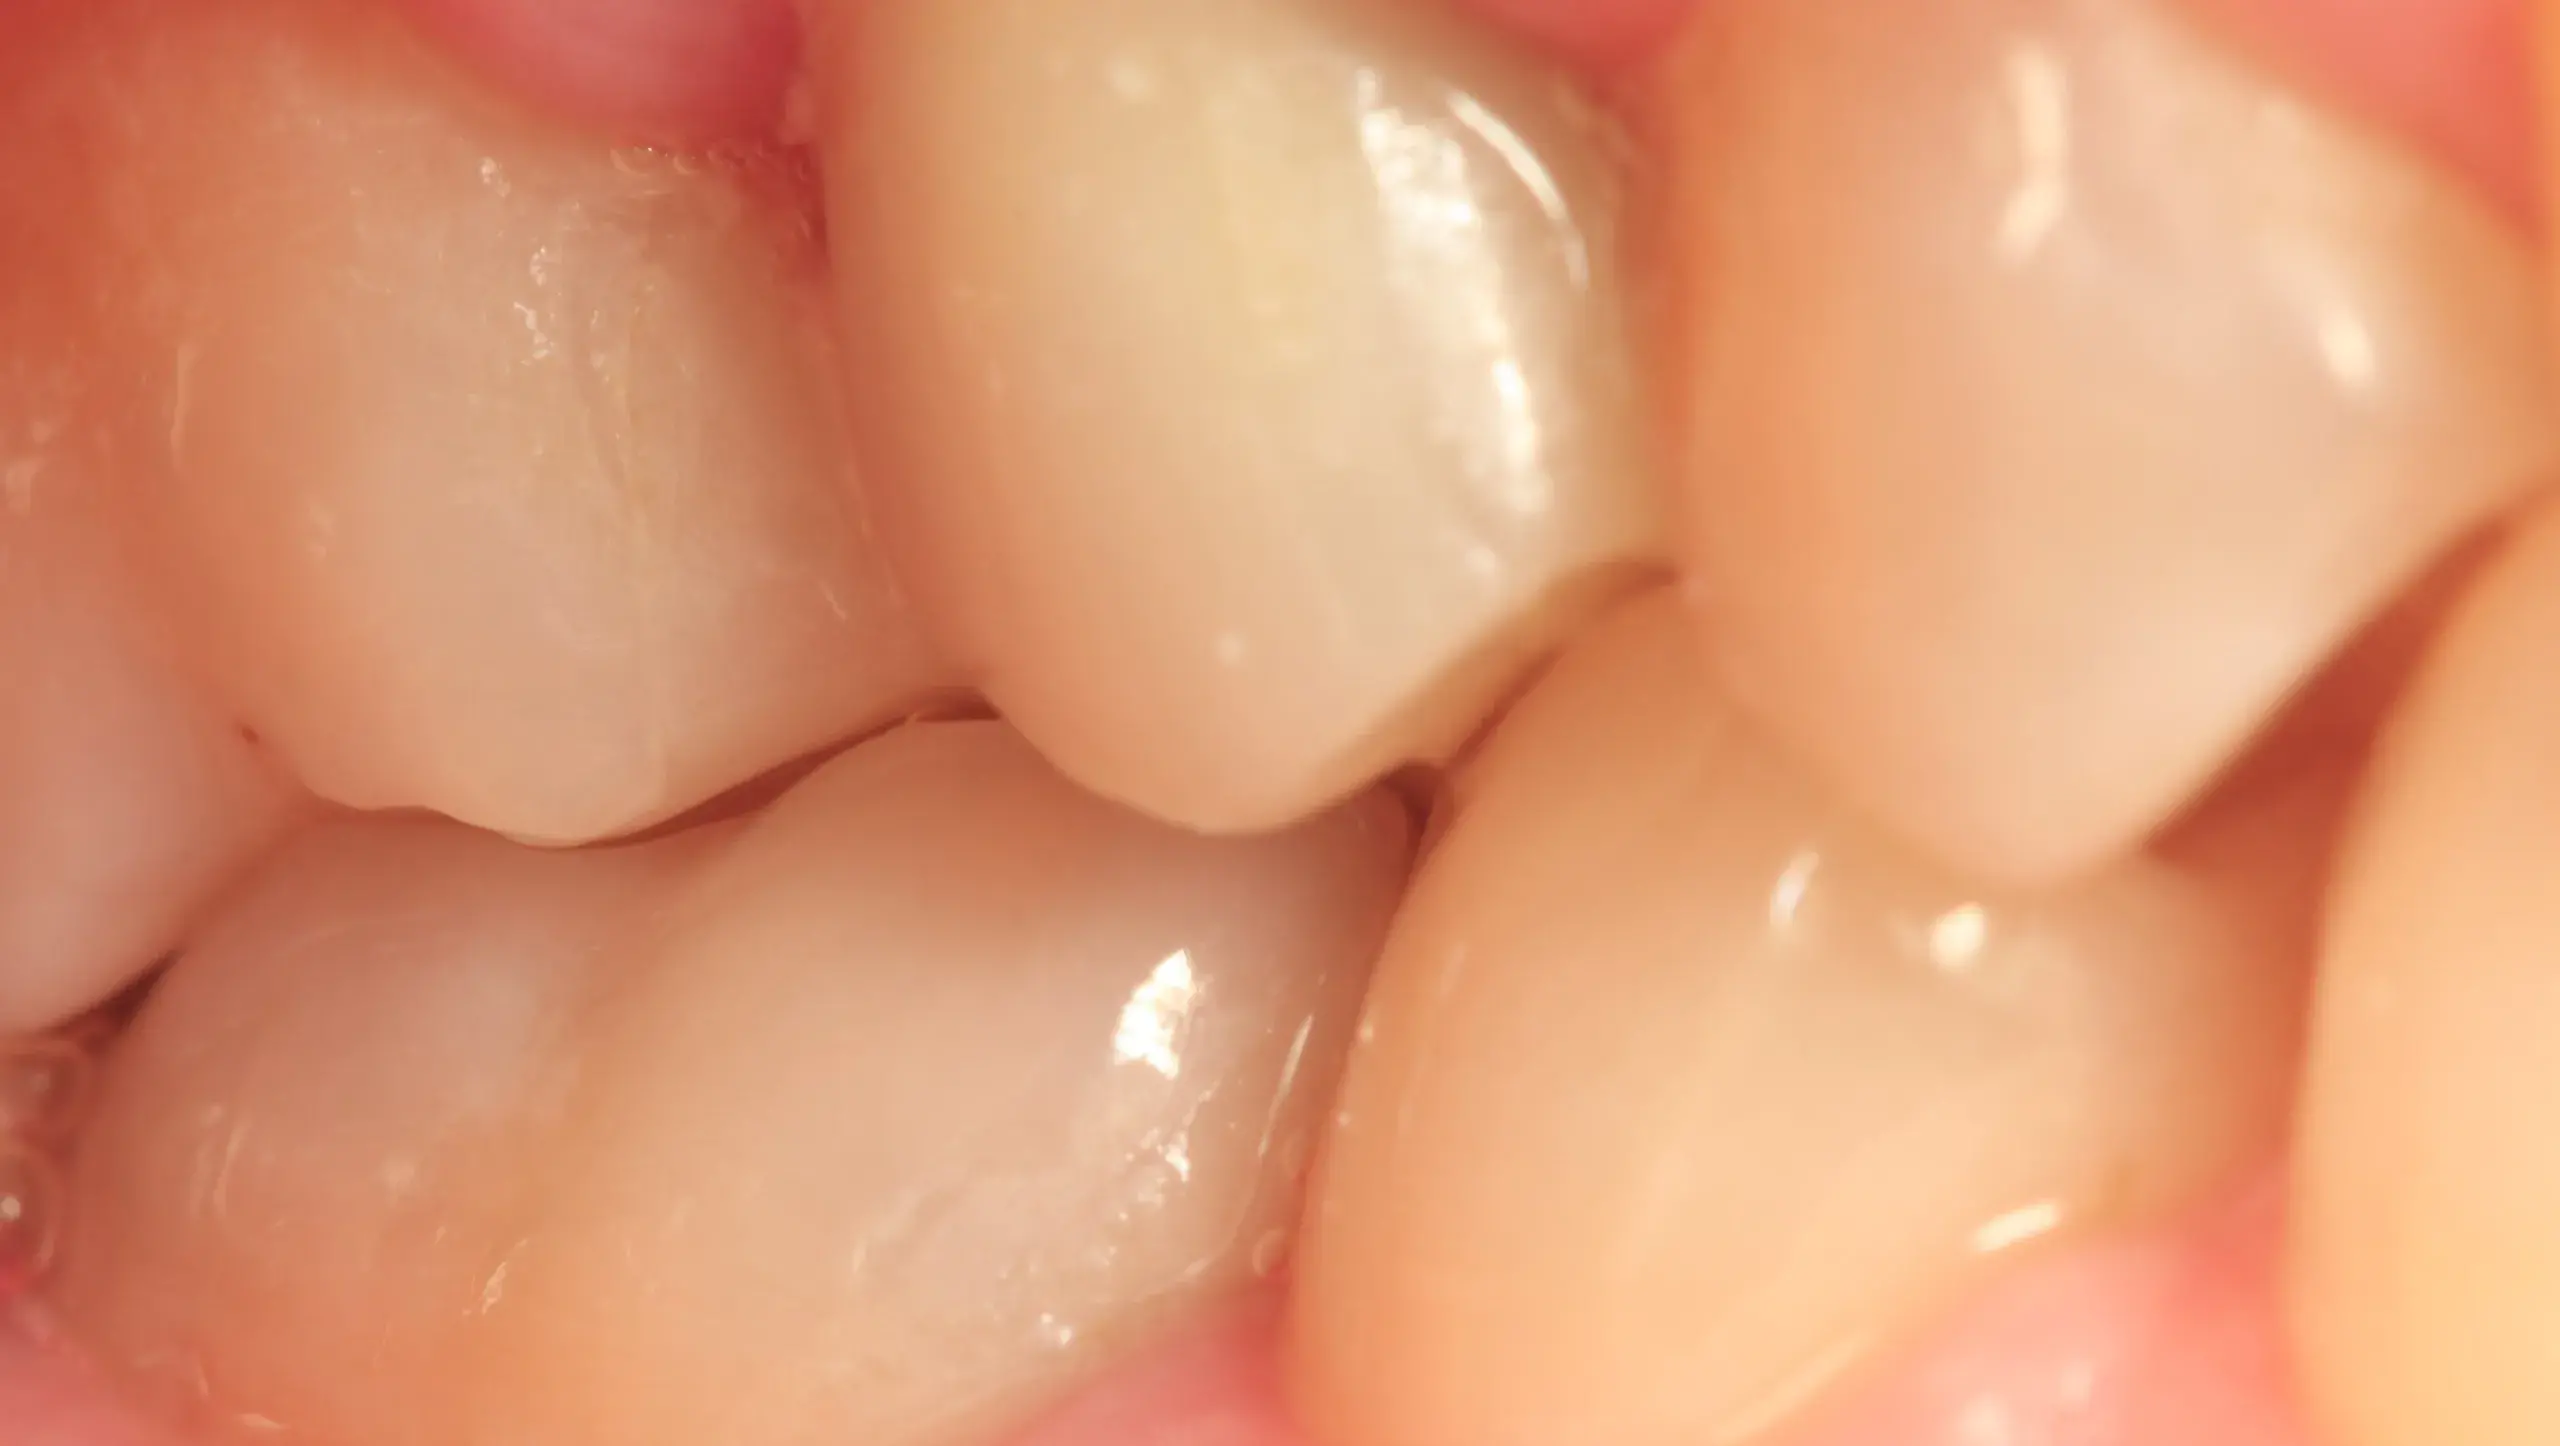

Caso clínico 5: Canino inferior incluido

Caso clínico 5: Canino inferior incluido El diagnóstico principal para este caso fue un canino inferior impactado.Antes de la ortodoncia:Canino impactado:El canino inferior derecho no había erupcionado en su posición…